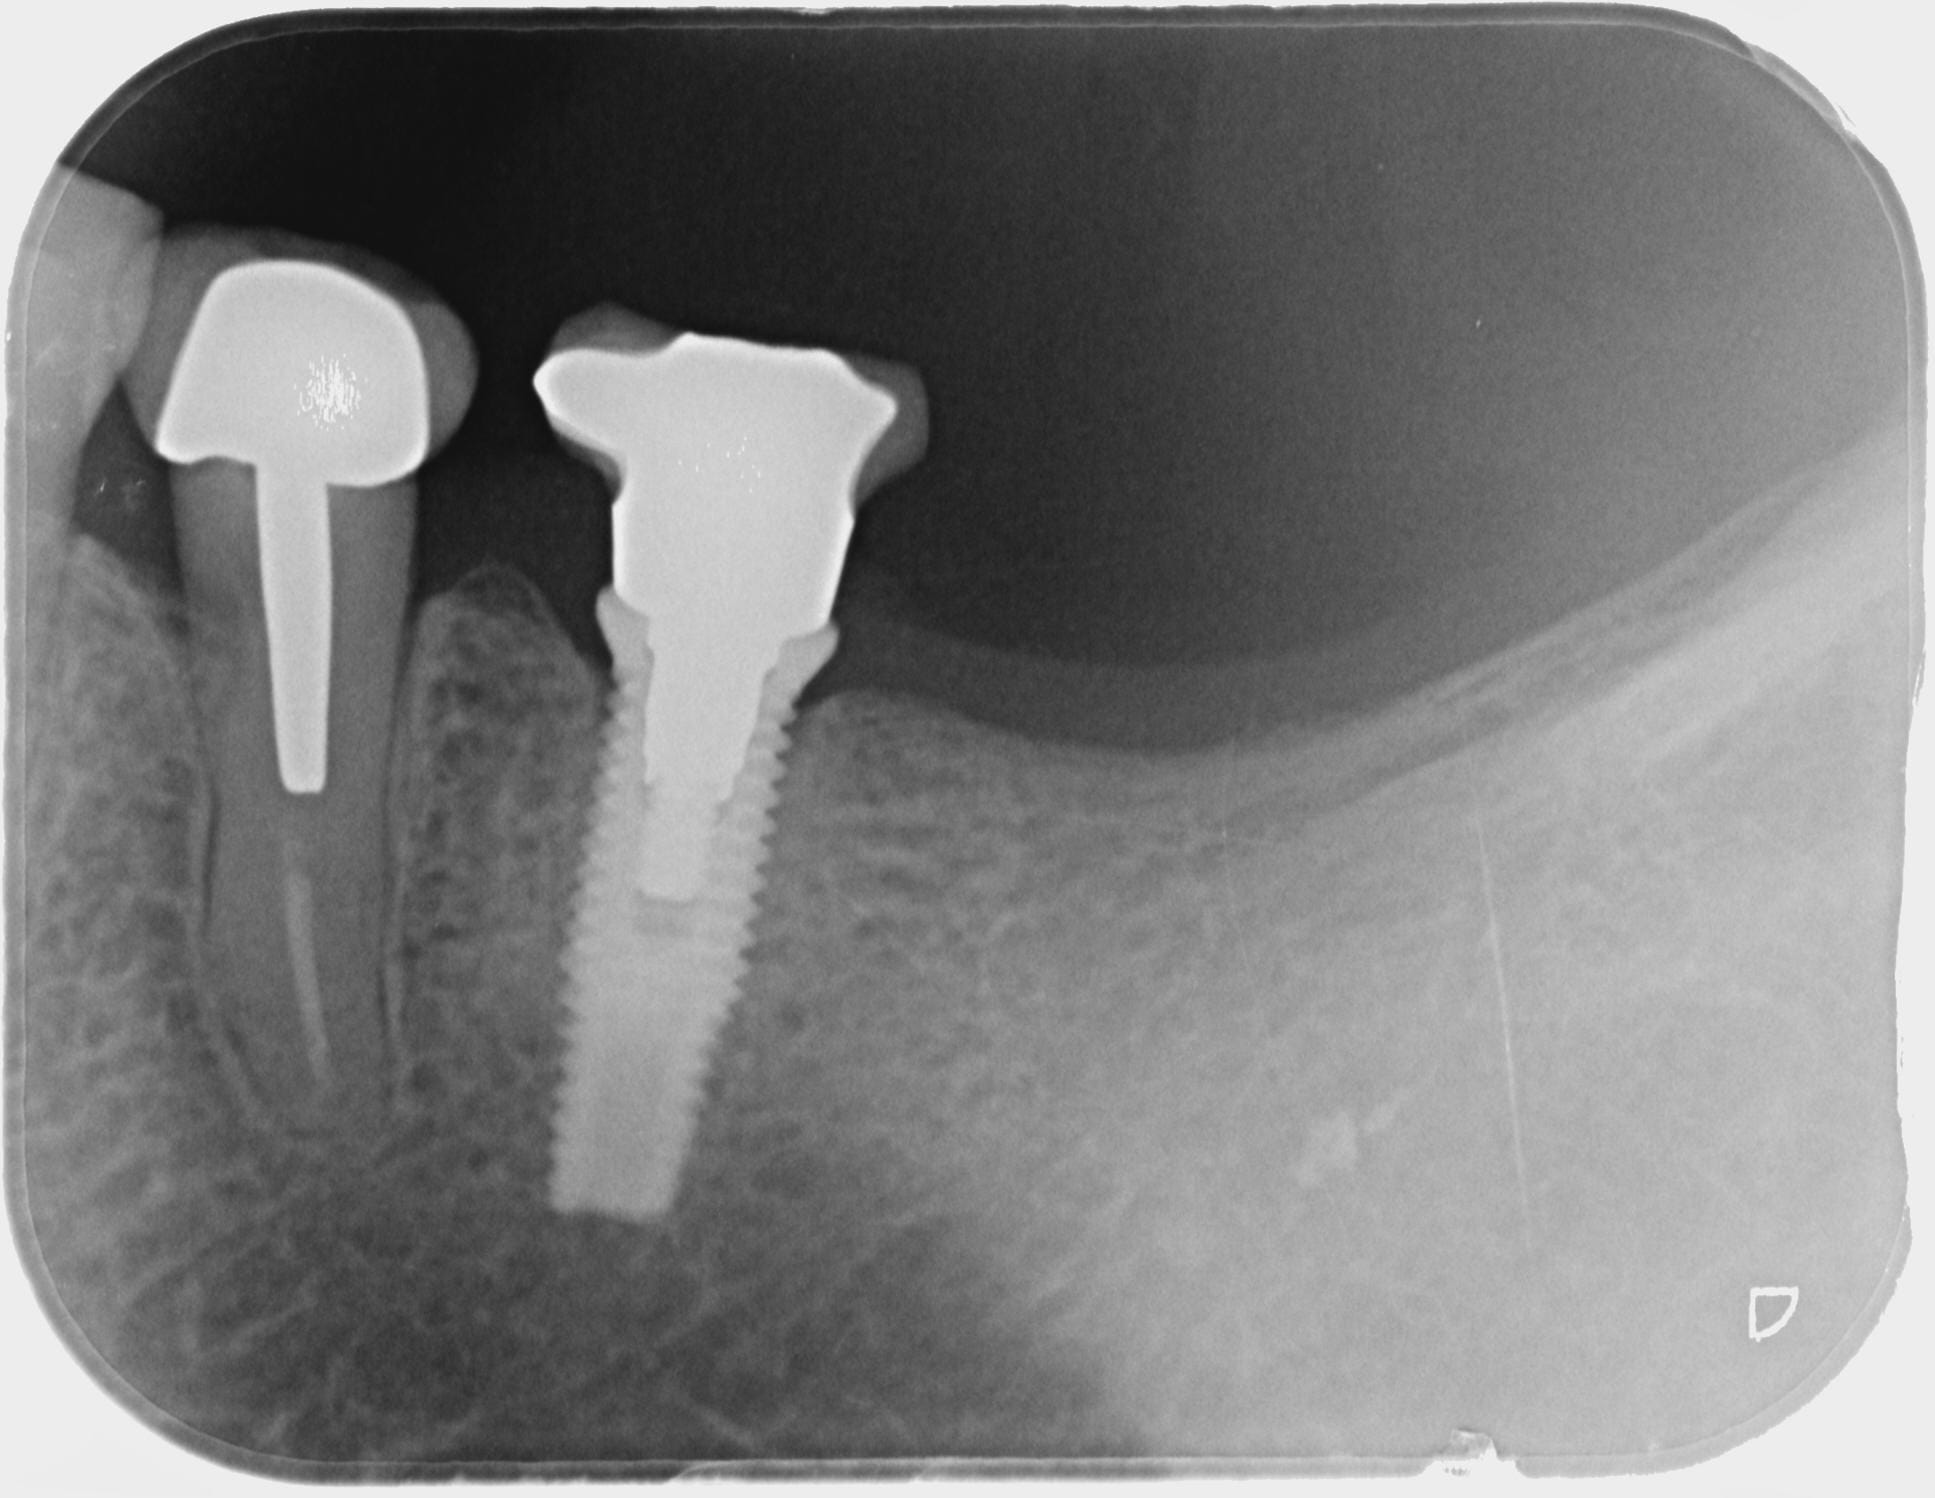

J'essaie d'identifier cet implant, je pense à un biomet 3i Osseotite, mais je suis vraiment pas certain, est-ce que les radio/photos parleraient à l'un de vous ?

Oui c’est du 3i, 100% certain